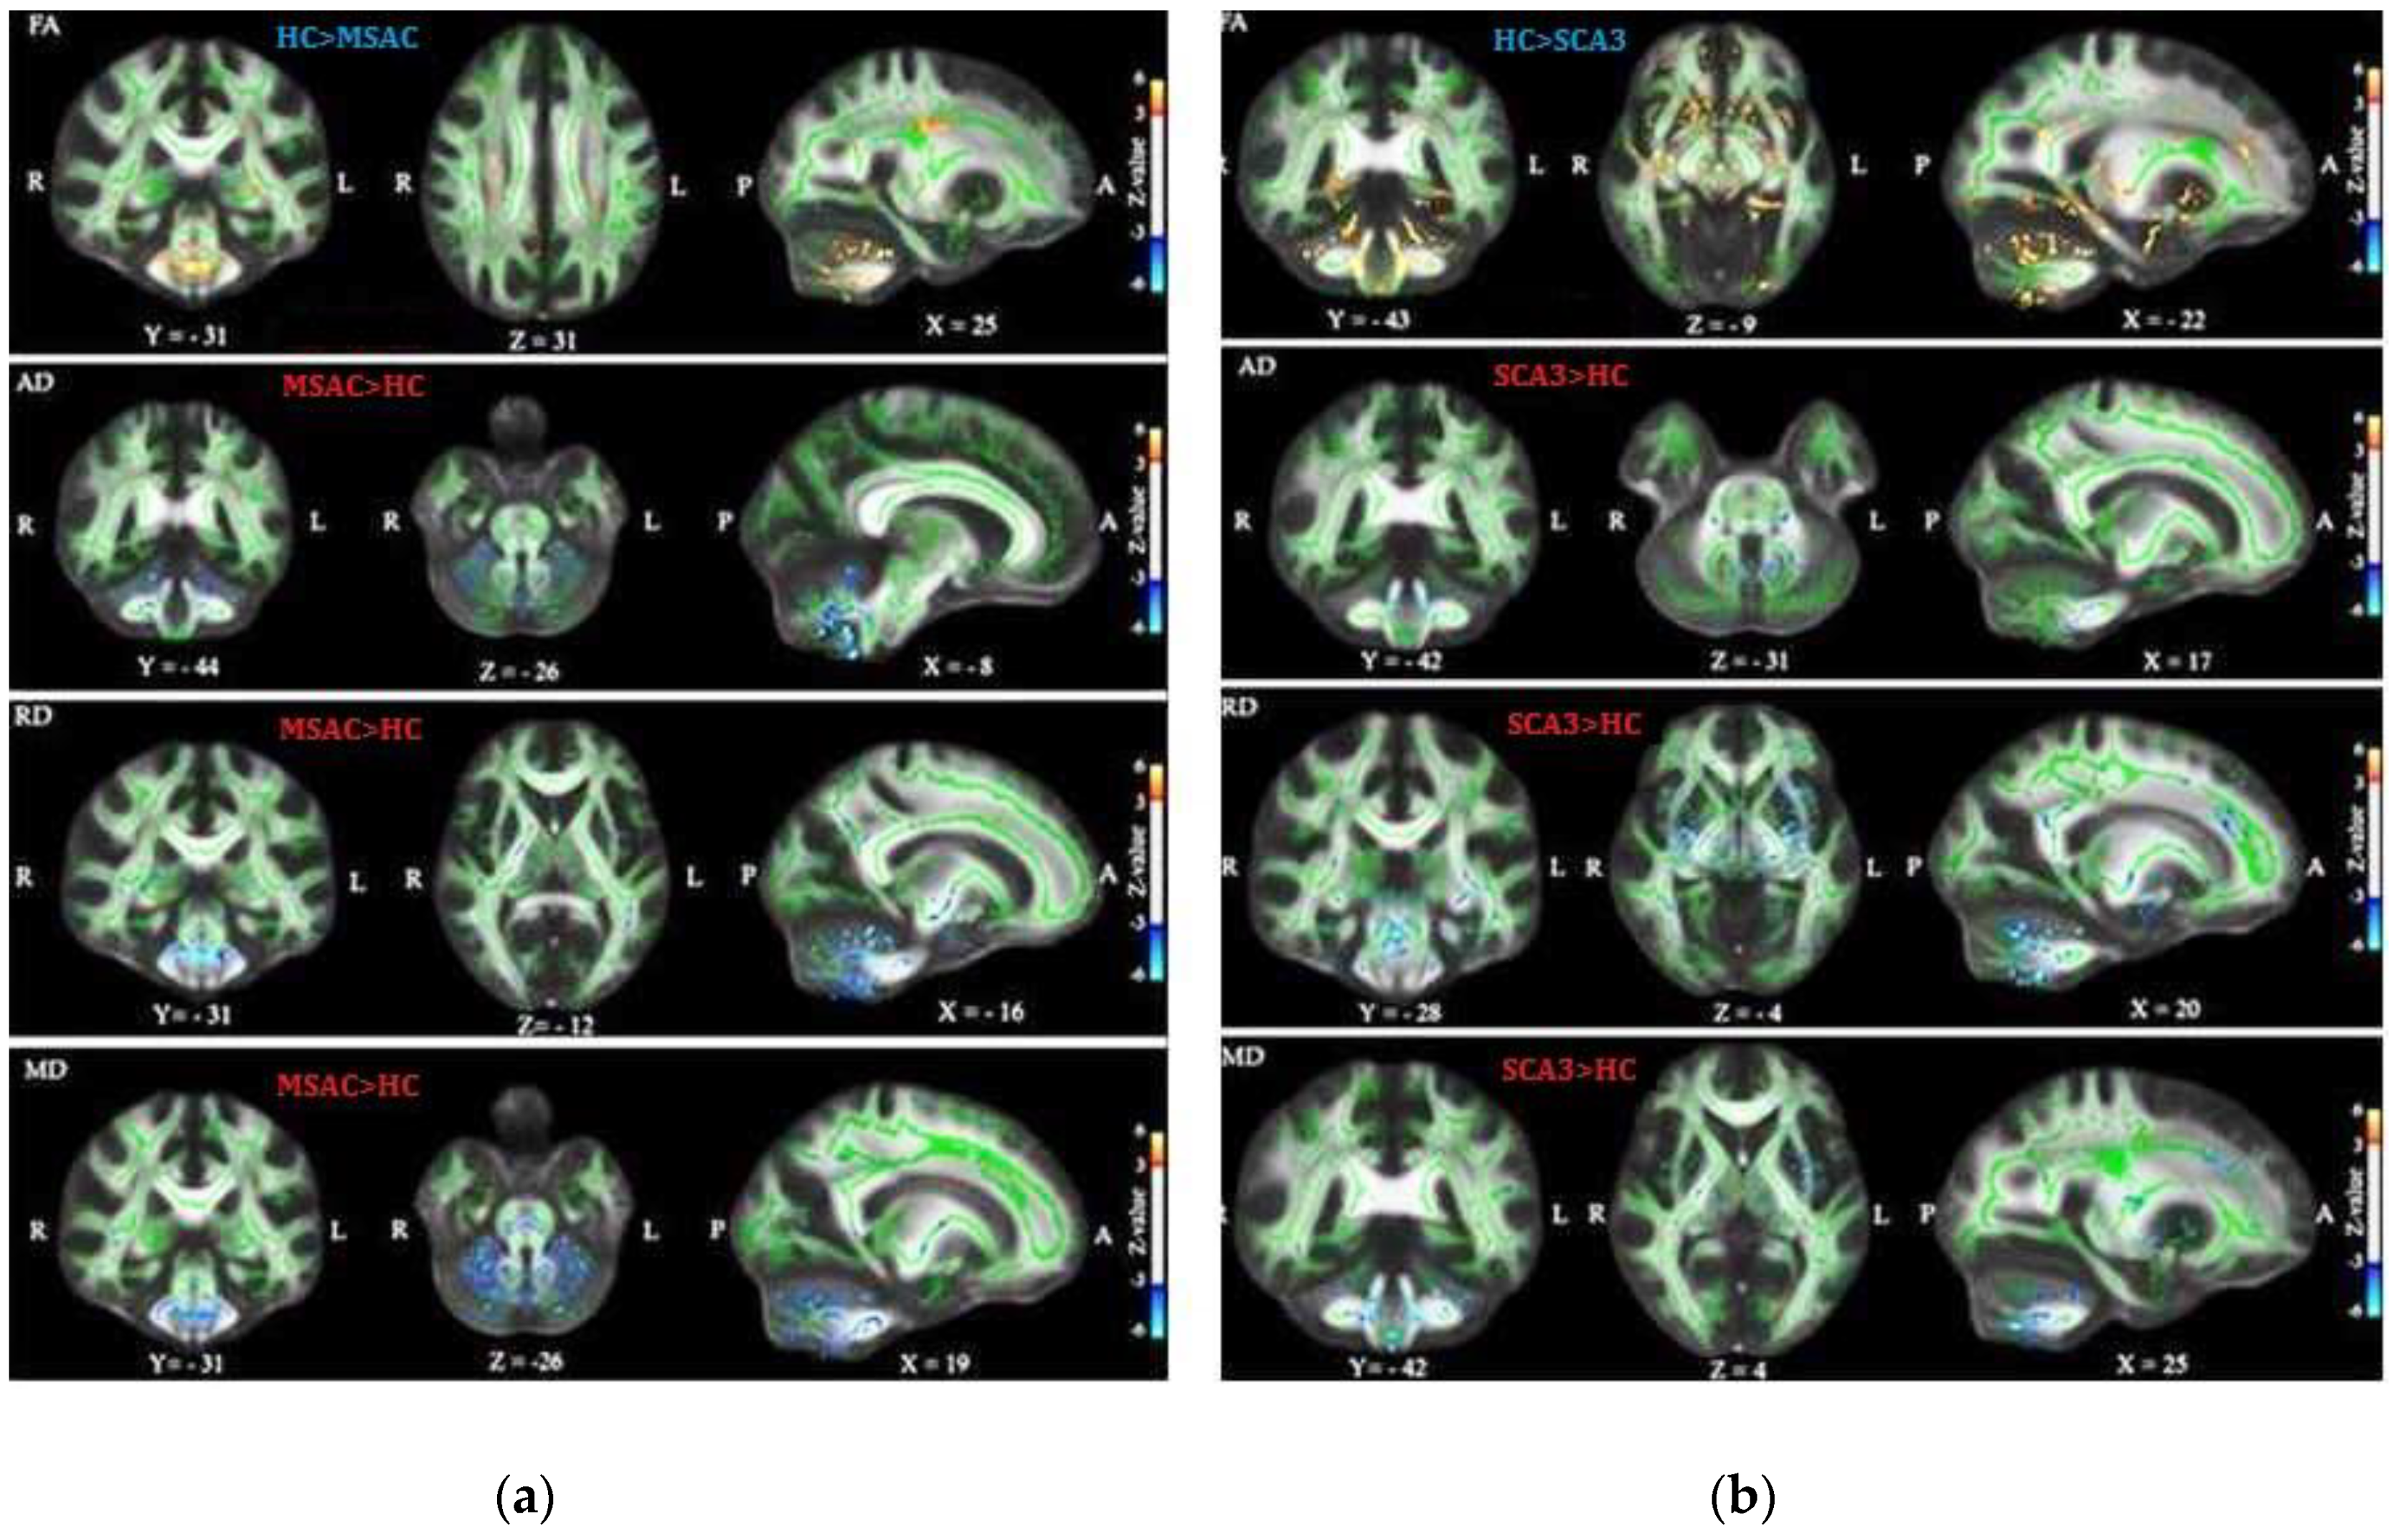

3.1. Patients with SCA3 or MSA-C Demonstrated Significant Decrease in FA and Increase in AD, RD, and MD

3.2. Patients with SCA3 Demonstrated Significant Decrease in FA and Increases in RD, AD, and MD